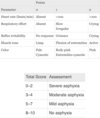

What are the components that make up APGAR scoring? What is the significance of APGAR socring?

APGAR scoring:

- five signs measured/observed in neonates 1 minute & 5 minutes after delivery

- PREDICTIVE on neonatal distress and need for intervention

- Components:

-

Most important:

- heart rate

- HR < 100 bpm: signifies arterial hypoxemia

- quality of respiratory effort

- heart rate

-

Least informative:

- color –

- healthy neonates have acrocyanosis @ 1 min from cold ambient temps (peripheral vasoconstriction)

- Persistent cyanosis- acidosis and pulm vasoconstriction most likely causes

- color –

-

Most important:

- Scores 3–7: Mild to moderately depressed function

- may respond to oxygen administration by face mask

- with or without positive pressure ventilation

- Score < 3: CONCERN

- consult NRP algorithm

Score 0-10